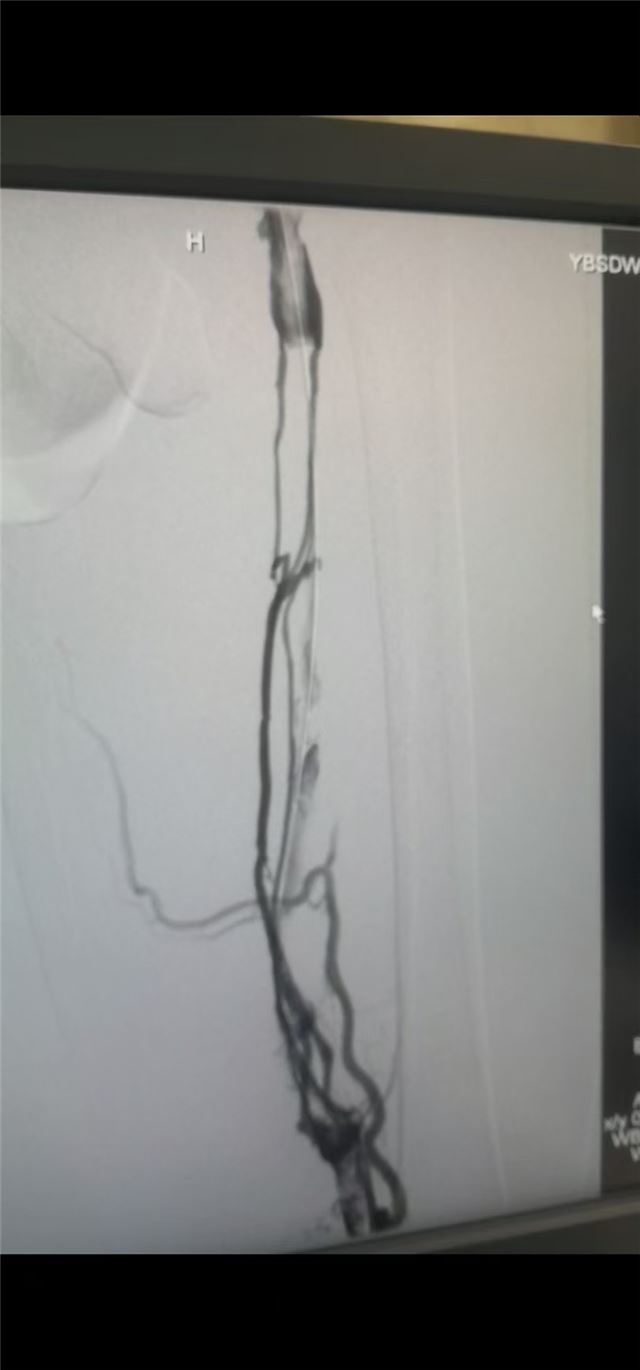

手术前下肢深静脉造影

手术后下肢深静脉造影